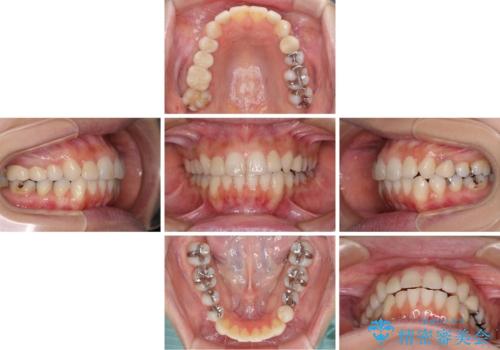

- 前歯のデコボコと矮小歯、更には痛みを感じる奥歯のむし歯を気にして来院された患者様です。

奥歯には根管治療が必要な歯があり、上顎側切歯は左右ともに矮小歯でした。

上下前歯のデコボコはワイヤーでもインビザラインでも対応可能でしたが、補綴治療が多く必要となることから、インビザラインでの矯正治療を行いながら、並行して補綴治療を行うこととしました。

まずは根管治療を行った上で矯正治療用の仮歯を装着し、矯正治療後半に補綴治療を並行して行うこととしました。

複数歯の補綴治療を行う場合、仮歯やセラミッククラウンを装着する度に保定装置を作り替える必要があり、その度に後戻りを起こす可能性が高くなります。

インビザラインであれば、矯正治療後半で補綴治療を行い、その後矯正治療を継続することでスムーズに治療を終えることができます。